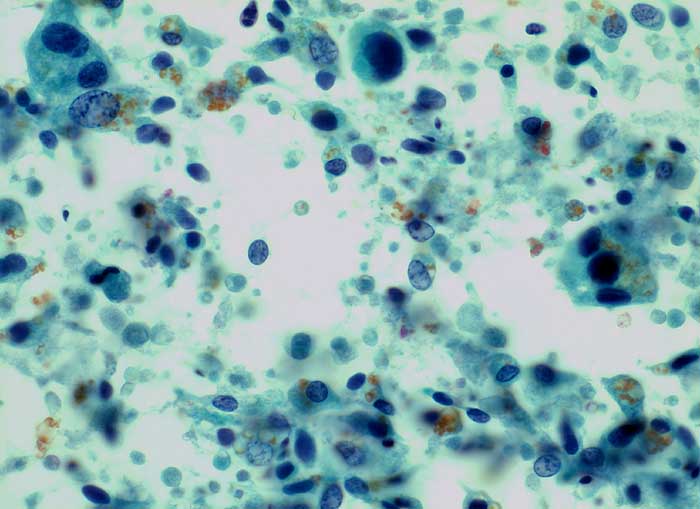

Samenblase, Spülzytologie: Ausgeprägte Pleomorphie. Vergrösserte Kerne mit vergröbertem Chromatin und intranukleären Vakuolen. Pyknotische Kerne. Polygonale und spindelige Zellen. Reichlich goldgelbe Lipofuszinkörner.

Bei einer Prostatamassage können Samenblasenepithelien in den Urin gelagen, welche wegen ihrer ausgeprägten Pleomorphie zu einer Karzinomfehldiagnose verleiten können. Das Lipofuszinpigment hilft auf die richtige Spur.